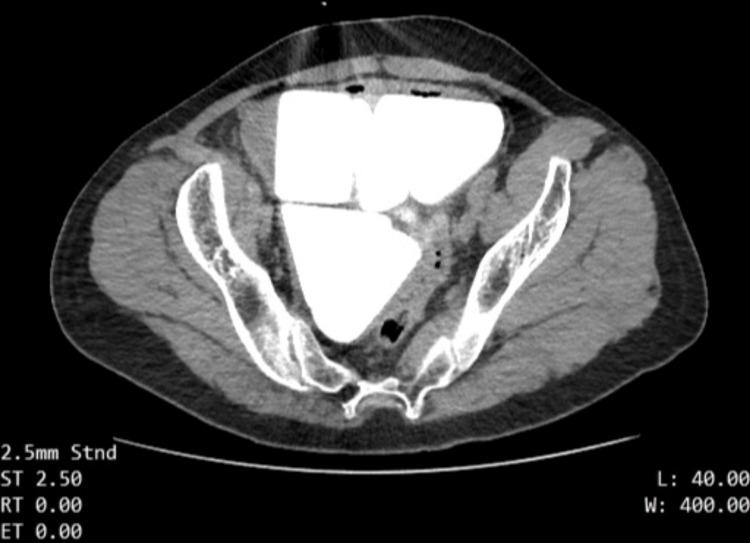

膀胱增大伴多发巨大结石:一例报告

Multiple Giant Stones in an Augmented Bladder: A Case Report.

Bladder stones are a common finding in urology practice although they are less common when compared to kidney and ureteral stones. This case report involves a male patient in his 40s with multiple giant bladder stones. The patient had neurogenic bladder disease due to spina bifida and had a history of bladder augmentation with continent urinary diversion when he was a child. He presented with difficulty in emptying bladder with clean intermittent catheterization. Open cystolithotomy was performed and six giant stones, five pyramid-shaped stones and a cube-shaped stone with a maximum diameter of 7 cm, were removed from the bladder. In our opinion, the rare occurrence of a high stone burden, stone weight and size, and geometric shapes of stones makes this case interesting. The patient was discharged from the hospital on the 10th day after the surgery and there were no postoperative complications.

摘要

膀胱结石在泌尿外科临床实践中较为常见,尽管与肾结石和输尿管结石相比相对少见。本病例报告涉及一名40多岁的男性患者,患有多发巨大膀胱结石。该患者因脊柱裂患有神经源性膀胱疾病,儿童时期有膀胱扩大术及可控性尿流改道术史。他表现为通过清洁间歇性导尿排空膀胱困难。实施了开放性膀胱切开取石术,从膀胱中取出了6块巨大结石,其中5块为金字塔形结石,1块为最大直径达7厘米的立方体结石。我们认为,如此高的结石负荷、结石重量和大小以及罕见的结石几何形状,使得该病例颇具趣味性。患者术后第10天出院,无术后并发症。